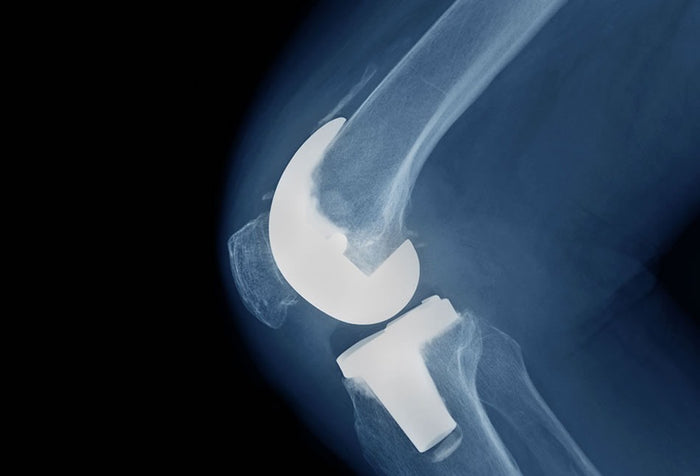

Published by our partners at Slocum Orthopedics demonstrates that our intervention for joint replacement surgery increases muscle cells pre surgery and creates a more favorable inflammatory environment post surgery. This builds on the outcomes studies that show enhance function and recovery.